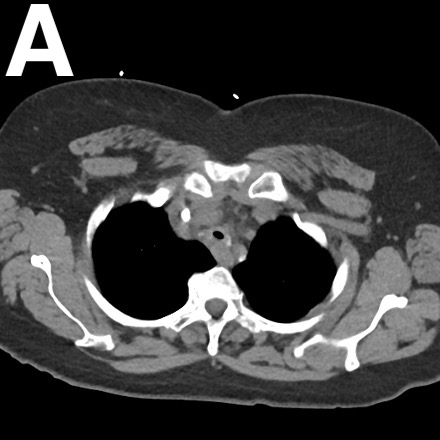

The patient received treatment for presumed bronchospasm with nebulized bronchodilators and inhaled corticosteroids. Given the persistence of her symptoms during follow-up approximately 1 month later, the patient was scheduled for a CT angiography of the chest to evaluate for pulmonary embolism or other intrathoracic pathology. The results showed no evidence of pulmonary embolism but indicated focal narrowing of the midthoracic trachea approximately 5 cm below the glottis (Figure 2). The residual lumen diameter at the greatest degree of narrowing was approximately 3 mm in the anteroposterior dimension and 7 mm in the transverse dimension.

Figure 2. An axial view (A) and sagittal view (B) of the CT angiography of the chest showed focal narrowing of the midthoracic trachea approximately 5 cm below the glottis.